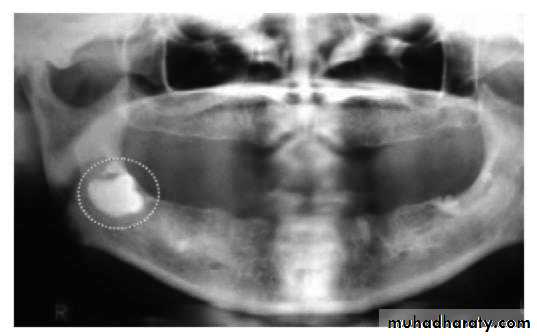

Removal of pathogenic bony conditions

( cyst, tumors)Cyst:…...enucleating or marsupialization